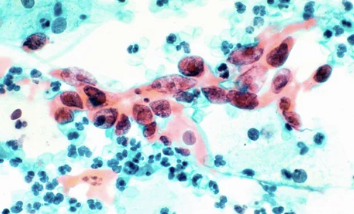

4-1. 자궁경부암 검사(세포진 검사, PAP 스미어)

- 자궁경부암을 조기 발견하는 가장 일반적인 검사입니다.

- 검사를 통해 비정상 세포를 발견할 수 있습니다.